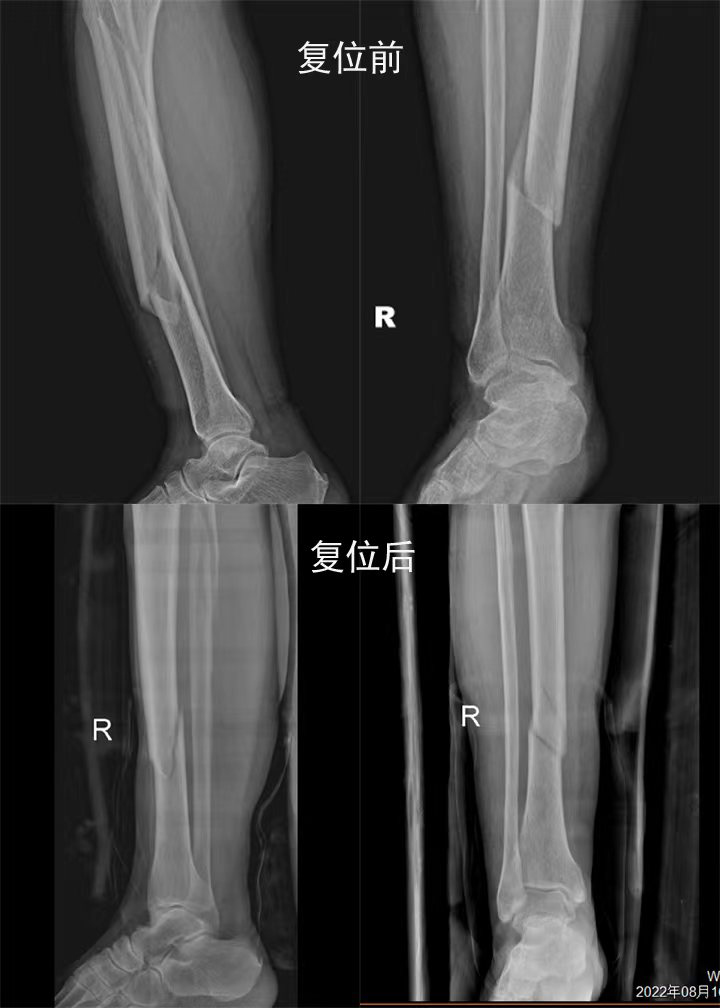

梁氏正骨-梁俊超正骨案例